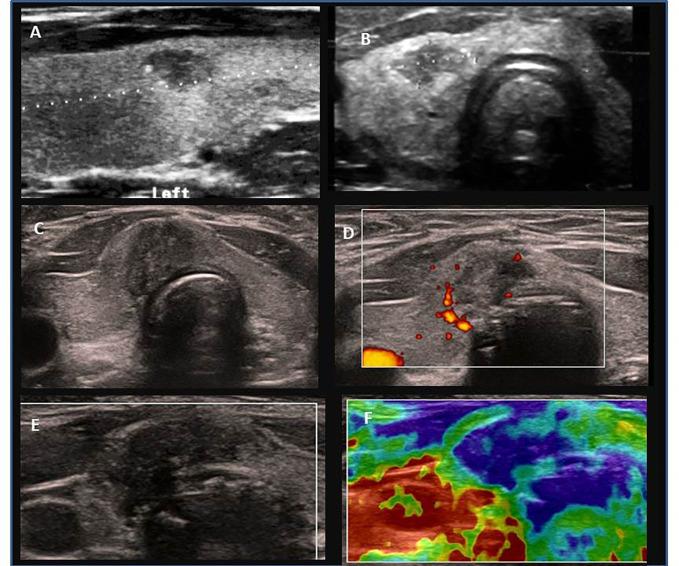

A retrospective analysis of medical records of 90 patients (69; 76.7% females). The mean age at PTC diagnosis was 13.8 years [range 6-18]. All patients were evaluated ultrasonographically before thyroid surgery. Thyroid nodules were categorised using the European Thyroid Imaging Reporting and Data System (EU-TIRADS PL), and cytopathology was assessed using Bethesda criteria. Neck ultrasound results and thyroid and autoimmune status were correlated with histopathological PTC assessment.

回顾性分析 90 例患者(69 例;女性占 76.7%)的病历。PTC 诊断时的平均年龄为 13.8 岁[6-18 岁]。所有患者均在甲状腺手术前进行超声检查。甲状腺结节采用欧洲甲状腺成像报告和数据系统(EU-TIRADS PL)进行分类,细针穿刺细胞学检查采用 Bethesda 标准评估。颈超声结果和甲状腺及自身免疫状态与组织病理学 PTC 评估相关。

The coexistence of PTC and AIT was found in 48.9% (44/90) of patients. The percentage of AIT was increasing with age; AIT was present only in 1/3 of prepubertal, close to 50% in pubertal, and over 60% in adolescent patients. The youngest patients (aged <10 years old) presented more often with goitre and lymphadenopathy and less often with AIT than adolescents (15-18 years of age). There were no differences in TPOAb, TgAb, and TSH levels between the age subgroups. Presurgical TgAb levels were higher than those of TPOAb in the youngest patients. Histopathological analysis revealed that the solid subtype was observed more often in prepubertal children and diffuse sclerosing in children below 14 years of age, whereas the classic subtype dominated in late pubertal. Univariate and multivariate analyses revealed that lymph nodes metastases (LNM) were associated with PTC diameter and fT4 level, whereas extrathyroidal extension with age and angioinvasion with PTC diameter and age. The correlations between age and fibrosis, and the presence of psammoma bodies in malignant tissues were close to significant. We did not observe an association between TSH levels and the presence of autoimmunity and PTC variables.

48.9%(44/90)的患者同时存在 PTC 和 AIT。AIT 的发生率随年龄增长而增加;AIT 仅见于 1/3 的青春期前患者,接近 50%的青春期患者,60%以上的青少年患者。年龄最小的患者(<10 岁)比青少年患者更常出现甲状腺肿和淋巴结病,而 AIT 较少。TPOAb、TgAb 和 TSH 水平在年龄亚组之间无差异。在年龄最小的患者中,术前 TgAb 水平高于 TPOAb。组织病理学分析显示,实体型多见于青春期前儿童,弥漫性硬化多见于<14 岁儿童,而经典型多见于青春期后期。单因素和多因素分析显示,淋巴结转移(LNM)与 PTC 直径和游离 T4 水平相关,而甲状腺外侵犯与年龄相关,血管侵犯与 PTC 直径和年龄相关。年龄与纤维化之间的相关性以及恶性组织中沙粒体的存在与显著相关接近。我们没有观察到 TSH 水平与自身免疫和 PTC 变量之间的相关性。